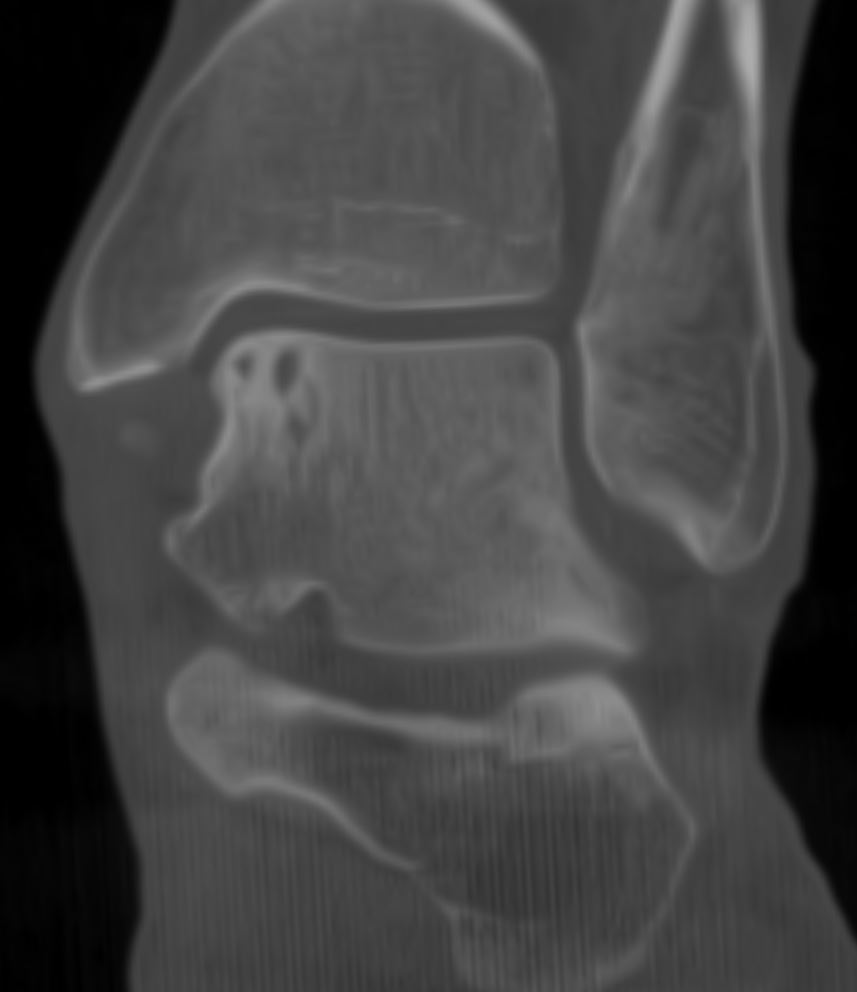

Home Schwerpunkte Krankheitsbilder Osteochondrale Läsion des Talus (OCL) – Ursachen, Symptome, MRT/DVT-Diagnostik & moderne Therapie DVT frontal Talus Zysten ocl 2023 bei Sx

DVT frontal Talus Zysten ocl 2023 bei Sx

OCL mediale Talusschulter ohen Trauma